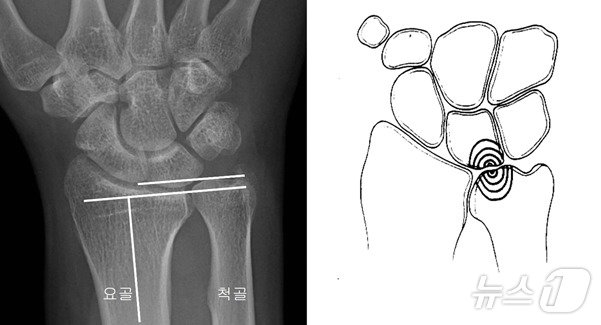

좌측의 그림처럼 손목에서 척골의 길이가 요골보다 긴 경우, 우측의 그림처럼 척골과 수근골 사이에 충돌이 일어나는 상태를 ‘척골충돌증후군’이라고 한다(중앙대학교병원 제공)